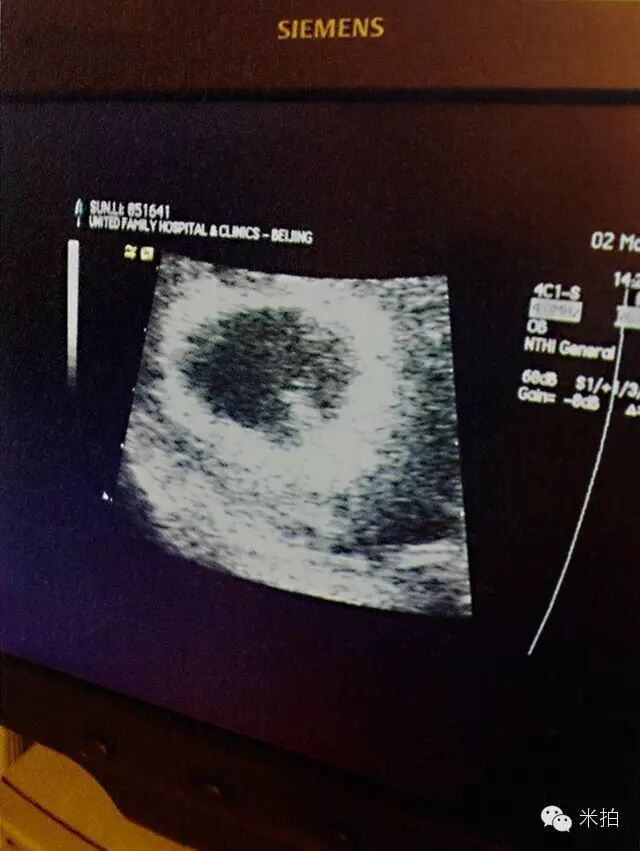

两个人都怀孕了

妹妹人儿就要来了

妹妹

2013年12月,妹妹降生,从那一刻起,我们踏上新旅程。从此,一家四口啦!